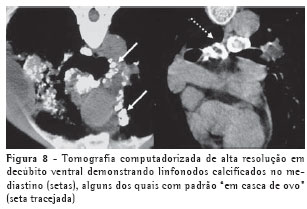

Podem também ser evidenciadas calcificações em linfonodos hilares ou mediastinais, por vezes periféricas, com padrão de "casca de ovo" (Figura 3).

Como as alterações predominam nas regiões posteriores, a TCAR deve ser sempre realizada em decúbito ventral, com técnica de alta resolução, cortes finos de 1 a 2 mm, intervalo entre os cortes de 10 mm, e sem injeção venosa do meio de contraste.

A TCAR apresenta ainda maior eficácia do que a radiografia para demonstração de linfonodomegalias ou de calcificações linfonodais (Figura 8).